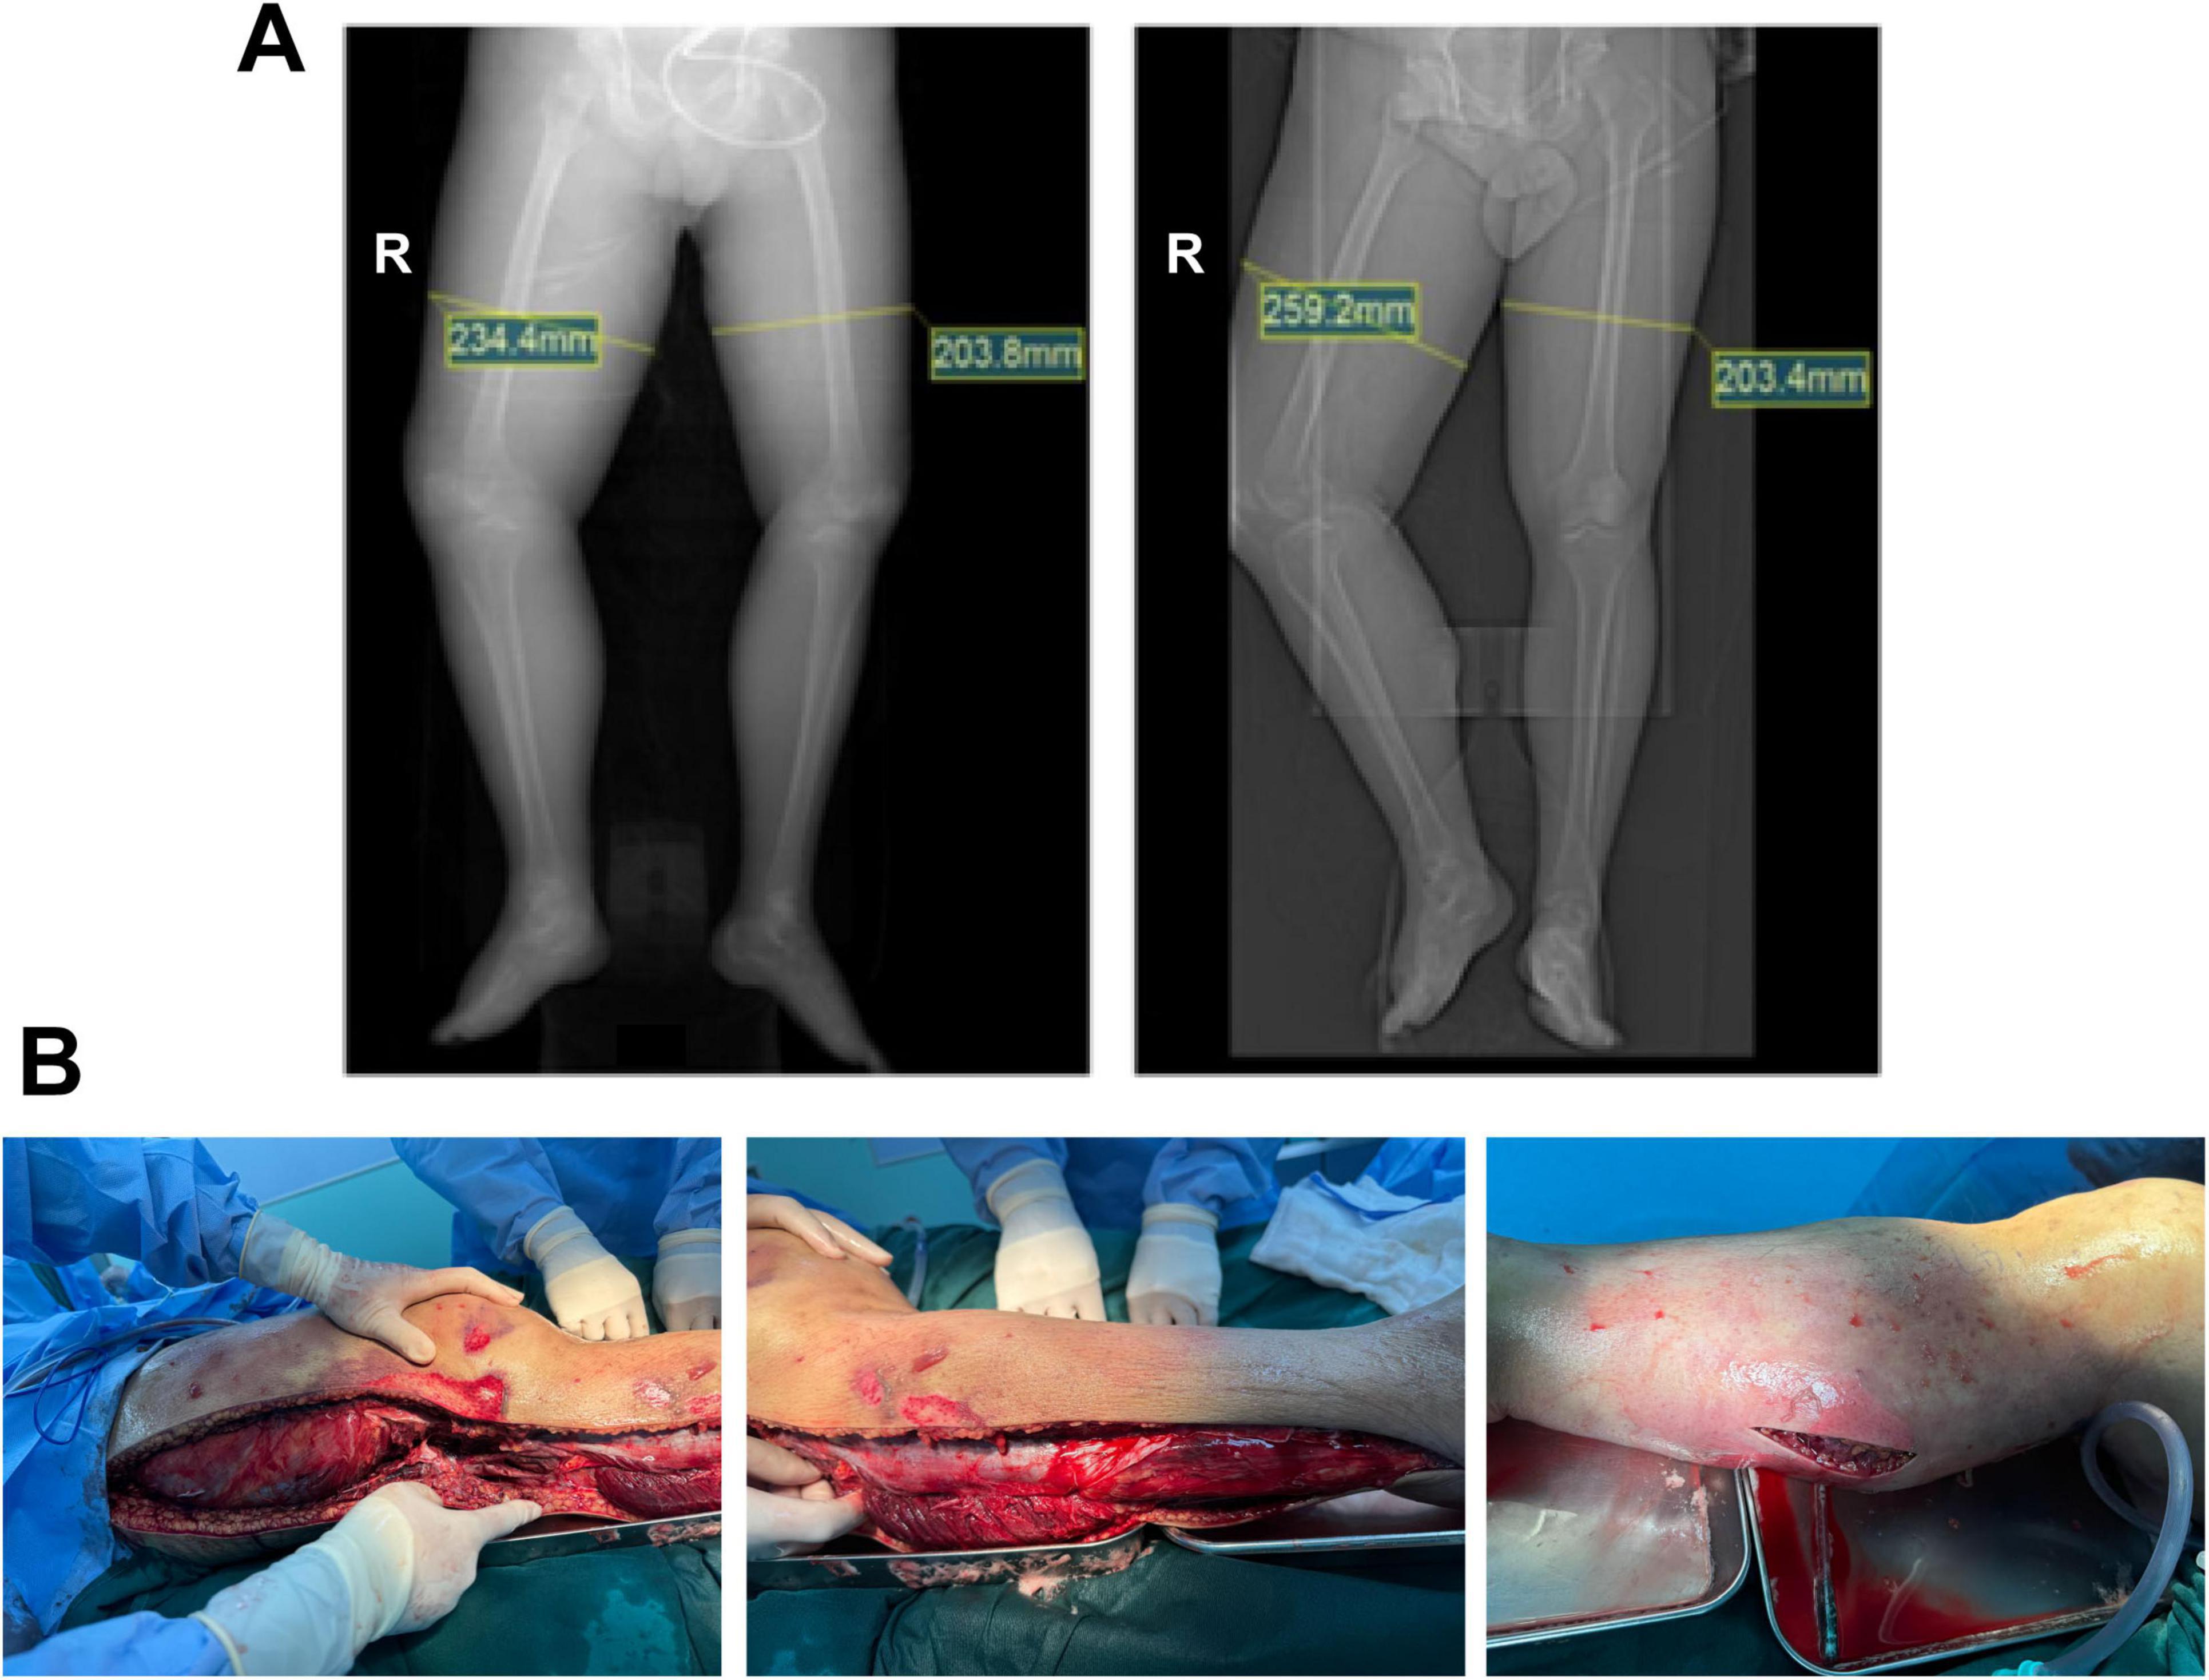

FIGURE 3

Preoperative imaging and intraoperative findings. (A, left) CT localization scan of both lower limbs at 02:17 on June 26, 2025, showed marked thickening of the right thigh soft tissue, measuring 234.4 mm (right thigh) and 203.8 mm (left thigh). (A, right) CT scan at 10:26 on June 26, 2025, indicated significant progression of right thigh soft tissue swelling, now measuring 259.2 mm (right thigh) and 203.4 mm (left thigh). (B) Intraoperative exploration revealed pronounced edema of the right lower limb fascia and areas of muscle that appeared gray-white and inelastic, consistent with necrotic changes and diagnostic for necrotizing fasciitis.